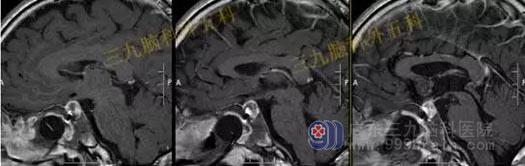

头部MR检查提示:鞍区短T1稍短T2异常信号影,大小约8mm×10mm×10mm,垂体受压下移,垂体柄受压后移。视交叉轻度受压上抬。鞍区异常信号影,考虑Rathke's囊肿可能性大。

手术过程:完善相关检查后行内镜经鼻蝶鞍区Rathke’s囊肿切除术,通过微创全切囊肿。

术后MR检查提示:经鼻蝶鞍区占位性病变切除术后改变,原病变已切除。